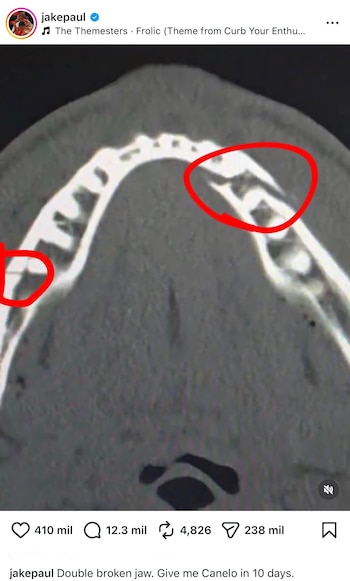

Luego del combate, Jake Paul difundió en sus redes sociales una radiografía en la que se aprecia la doble fractura de mandíbula que sufrió durante la pelea.

En esa misma publicación, el estadounidense aprovechó para lanzar un desafío directo a Saúl “Canelo” Álvarez al escribir: “Doble mandíbula rota. Dame a Canelo en 10 días”.